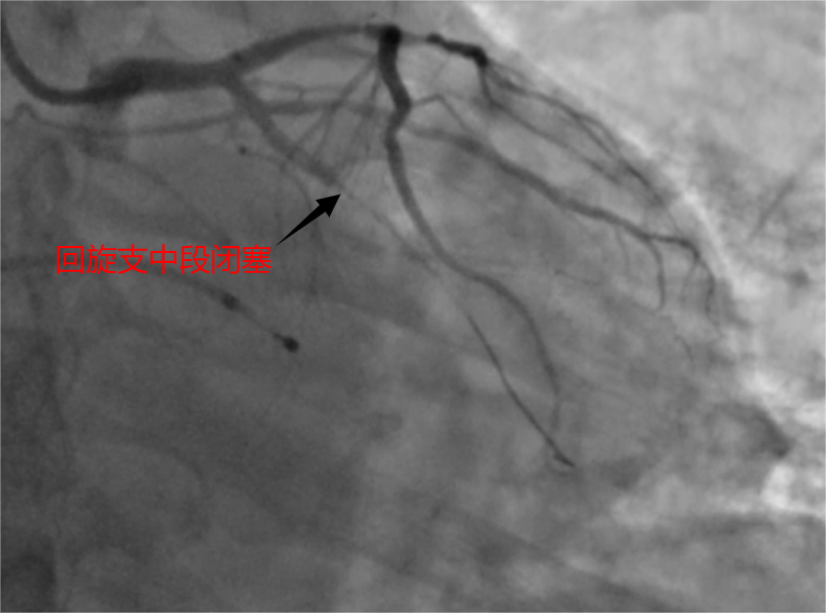

介入中,徐先增团队查出,杨先生的急性心肌梗塞由回旋支中段闭塞引起,于14时11分成功将血管重新开通,并为其植入一枚支架。从患者到达医院到血管开通,仅用时31分钟,远低于抢救标准所要求的90分钟,刷新了医院救治急性心肌梗死血管开通时间记录。术后复查造影显示,支架贴壁良好,无残留狭窄,杨先生生命体征平稳,胸痛症状消失。

患者急性心肌梗塞由回旋支中段闭塞引起